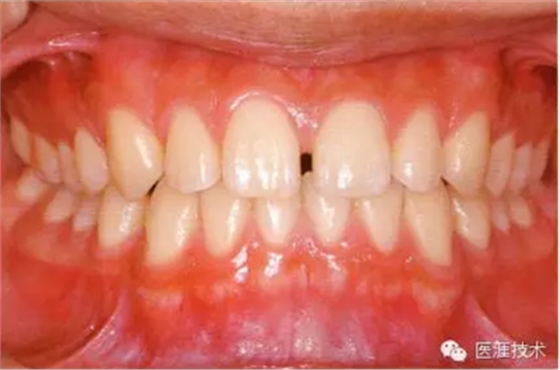

患牙齦炎的牙周組織的臨床圖像

22歲男性牙齦炎的臨床圖像

22歲男性,抽煙(1天約15根,煙齡5年)。刷牙狀態(tài)不佳。抽煙者特有的纖維性牙齦,未見(jiàn)發(fā)紅、腫脹。探針觸診,所有部位均出血。X線牙片未見(jiàn)骨吸收,診斷為牙齦炎。